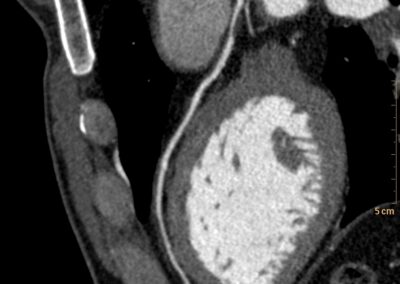

Τρισδιάστατη και δισδιάστατη απεικόνιση των στεφανιαίων αγγείων όπου διακρίνεται σημαντική στένωση λίγο μετά την έκφυσή του πρόσθιου κατιόντα κλάδου